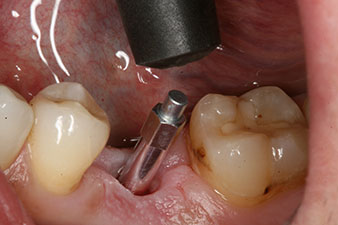

Implantat

Fig. 3: After preparation with the Implantmed implantology motor, an implant (diameter 4 mm, length 12 mm) was screwed in by the motor at a torque of 43 Ncm.

The implant was placed as planned after thorough removal of the granulation tissue (blueSky, bredent).